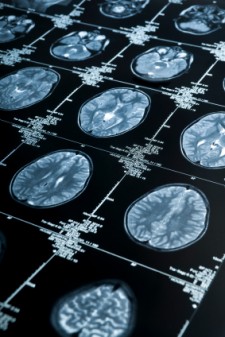

英国《经济学家》杂志10月31日报道称,过去,读心术或许只存在于科幻小说中。但在不久之后,这种情况就可能被打破。在大脑扫描成像技术领域,美国加利福尼亚州大学伯克利分校的一个研究小组日前取得了突破性进展,他们研发的技术可以让测试者“观看”到自己大脑思维中的动态图像,这是迄今已经获得证实的最令人惊讶的“读心术”。研究发现,大脑的神经活动能够直接被破译,也就是说人们的思想无需语言就能够被解读。